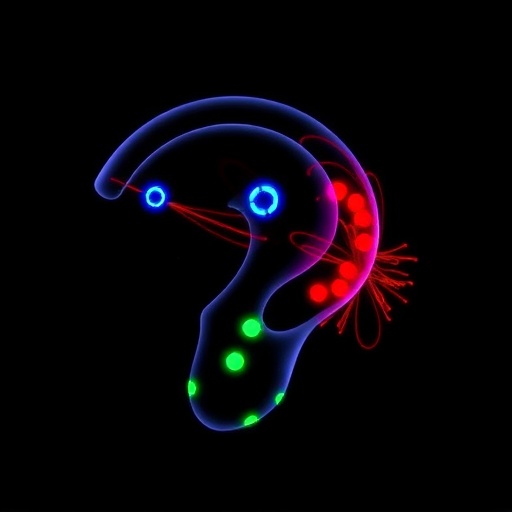

This pioneering research employed an innovative peptide display library, inserting nine-amino-acid motifs onto the capsid of the AAV1 serotype. By screening this diversified capsid library within cochlear tissues, the researchers successfully identified peptide insertions that substantially increased viral transduction efficiency in hair cells and their supporting cell counterparts. These engineered AAV vectors displayed a remarkable shift in cellular targeting profiles, governed by the inserted peptides’ ability to enhance virus-cell surface interactions and facilitate internalization into target cells. This targeted modification moves beyond the limitations of parental AAV1 vectors, achieving robust transduction at lower viral titers and potentially minimizing systemic exposure.

Mechanistically, the study hypothesizes that the introduced peptides serve as ligand-mimics or receptor-binding motifs that enhance viral docking and endocytosis in inner ear cells. This peptide-enabled tropism could redirect vector uptake through alternative receptors or co-receptors distinct from those engaged by native AAV1 capsids. Such a mechanism implies not only improved binding affinity but also altered intracellular trafficking pathways that may enable more efficient genome release and expression within target cells. These insights provide a molecular foundation for the design of next-generation AAV vectors with tissue-specific tropisms.

Importantly, the vectors engineered in this study demonstrated superior transduction efficiency in both sensory hair cells and supporting cell populations, broadening the therapeutic utility across multiple cell types involved in cochlear function and pathology. Supporting cells play critical roles in hair cell maintenance, homeostasis, and regenerative signaling; thus, efficient gene delivery to these cells opens new avenues for therapies aimed at preservation and repair of sensorineural hearing loss. The ability to target diverse cell types within the cochlea with a single vector enhances the prospects for combinatorial gene therapies addressing complex inner ear disorders.